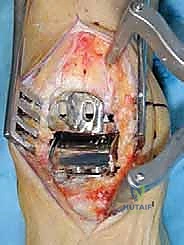

الخطوات الجراحية التفصيلية لزراعة مفصل HINTEGRA

تُجرى العملية عادة تحت التخدير النصفي أو العام، وتستغرق حوالي الساعتين إلى ثلاث ساعات. الدقة هنا تقاس بالمليمترات وأجزاء الدرجة الزاوية.

1. الشق الجراحي والوصول للمفصل

يقوم الجراح بإجراء شق أمامي طولي (Anterior Approach) في منتصف الكاحل. يتم إبعاد الأوتار والأوعية الدموية والأعصاب بعناية فائقة (هنا تتجلى أهمية مهارات الجراحة الدقيقة التي يمتلكها الدكتور هطيف) للوصول إلى محفظة المفصل.